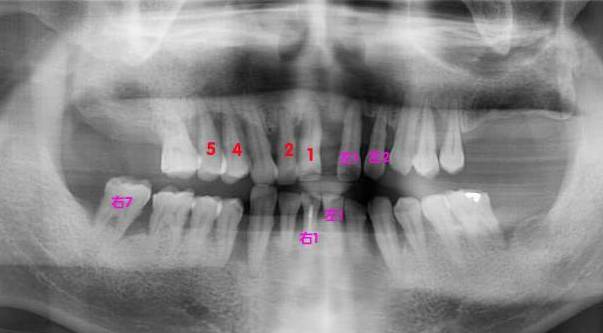

【byb.cn 大道至簡】2015年1月10日,我同時拔掉了4顆牙,即右上1、2、4、5顆牙,保留了3、6;與此同時,我還將在1月14日,繼續(xù)拔4顆牙,即左上1、2,左下1、右下1和右下7。換言之,在4天之內,我要拔掉9顆牙。

這次拔完牙之后,我上面還留有5顆,下面還留有9顆,共計14顆真牙,其余的牙,將被活動義齒所取代。

紅色的,是在1月10日拔掉的牙,粉色的,是即將在1月14日拔掉的牙

檢查是否需要拔掉智齒,也很簡單,照個片子就行了,不過100元左右,現在好一點的口腔門診都有,1分鐘就完成,直接可以在電腦和手機上看到你的牙齒的健康狀況。如果有條件,可過2年拍攝一張,以便做對比參照。